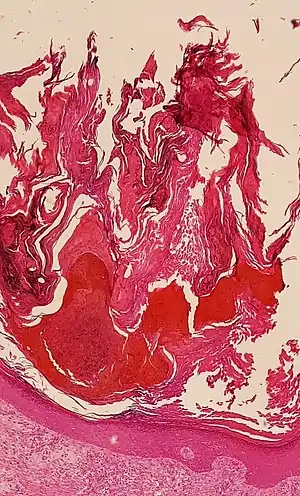

![]() Histologic image of human epidermis in thick skin. | |

The stratum corneum is the dead tissue that performs protective and adaptive physiological functions including mechanical shear, impact resistance, water flux and hydration regulation, microbial proliferation and invasion regulation, initiation of inflammation through cytokine activation and dendritic cell activity, and selective permeability to exclude toxins, irritants, and allergens.[5] This layer is composed of 15–20 layers of flattened cells with no nuclei and cell organelles. Their cytoplasm shows filamentous keratin. These corneocytes are embedded in a lipid matrix composed of ceramides, cholesterol, and fatty acids.[6]

The thickness of the stratum corneum varies throughout the body. In the palms of the hands and the soles of the feet (sometimes knees, elbows,[9] knuckles,) this layer is stabilized and built by the stratum lucidum (clear phase) which allows the cells to concentrate keratin and toughen them before they rise into a typically thicker, more cohesive SC. The mechanical stress of heavy structural strain causes this SL phase in these regions which require additional protection in order to grasp objects, resist abrasion or impact, and avoid injury. In general, the stratum corneum contains 15 to 20 layers of corneocytes. The stratum corneum has a thickness between 10 and 40 μm.